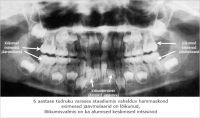

Eesmärk: Suu ja hammaste ülesannete kordamine, hammaste tähtsuse selgitamine ja näitlikustamine. Piima- ja jäävhammaste arvu, lõikumise nende tähtsuse ja vahetumise selgitamine.

Teises peatükis tutvutakse suuõõne sisemusega, erinevate hambatüüpide ja nende funktsioonidega.

Samuti õpitakse tundma hamba ehitust ning selgitatakse piima- ja jäävhammaste ning sülje tähtsust.